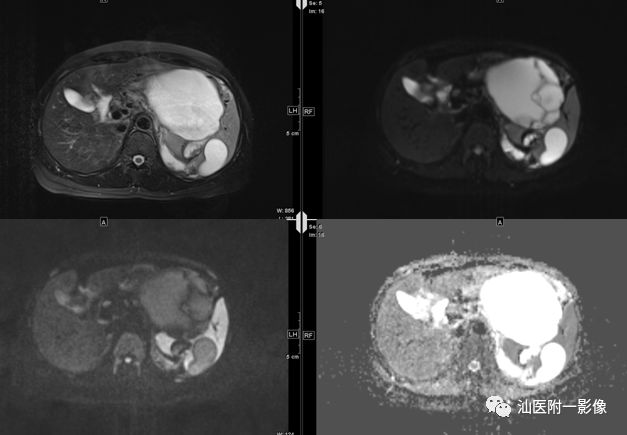

病例一 胰腺先天性囊肿